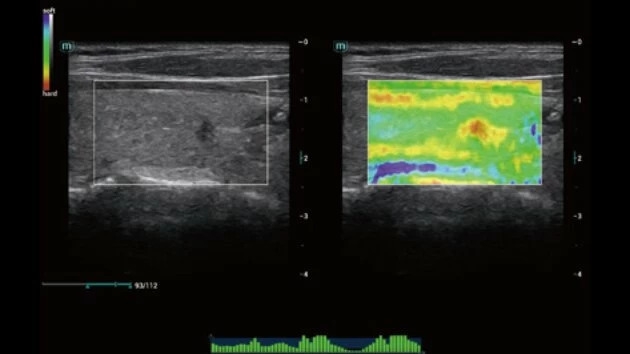

Эластография:

Компрессионная, Сдвиговая

Эластография сдвиговой волной/Эластометрия:

Да

Компрессионная эластография: